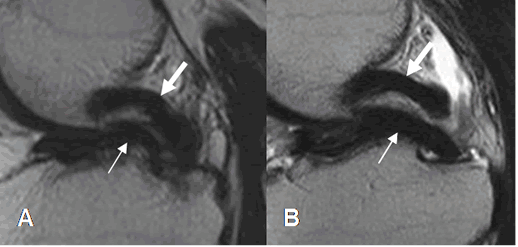

Fig 68. Ruptura meniscal dudosa.

A y B: RM sagital en T1. Imágenes hiperintensas y en sentido oblicuo, sobre el cuerno posterior del menisco interno. La completa comunicación con el borde inferior, es difícil de determinar con certeza.